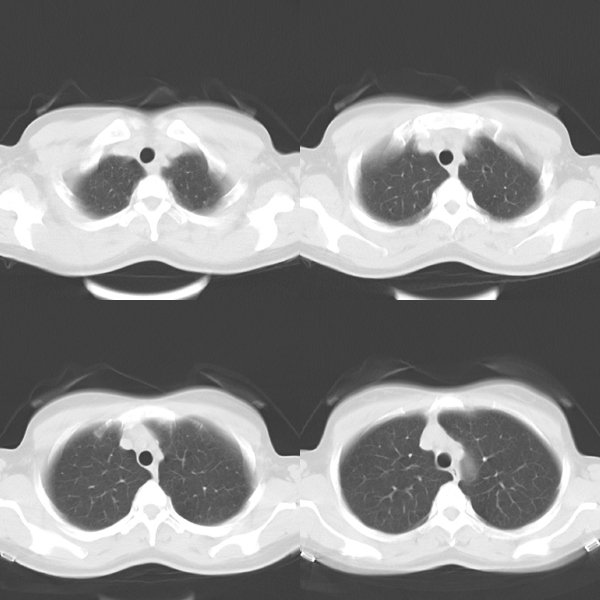

标题: CT19623:F40y,肋骨改变。

40岁女性,双侧胸部疼痛,以左侧为明显1+年。余无明显异常。

左侧肋骨单发膨胀性病变,皮质连续,病史较长,首先考虑良性病变:骨纤可能性大。